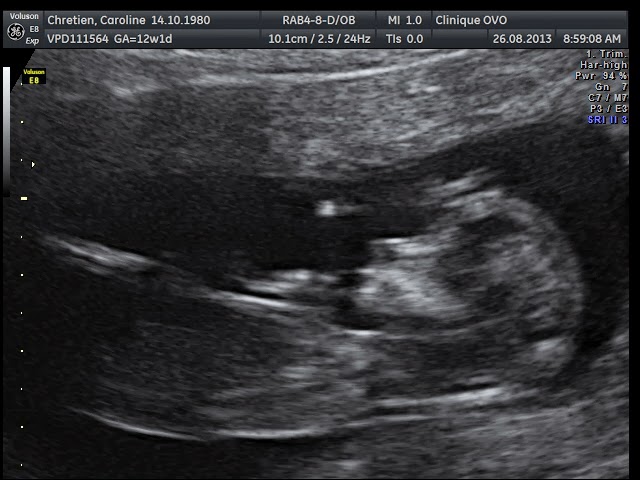

C'était notre écho de la clarté nucale ce matin. Elle sert à dépister la trisomie 13, 18 et 21, le spina-bifida entre autre.

La clarté nucale est à 1,54 (mm je crois?), les mesures de bébé retranchent 5 jours à ma date probable d'accouchement (selon les mesures, je suis à 12 6/7 SA). Mais bon, puisque c'est une FIV, c'est quand même impossible.. enfin!

Bébé vu de côté au complet. Tête à droite, corps au milieu, et on voit des bouts de bras/mains/ pieds/cordon ombilical